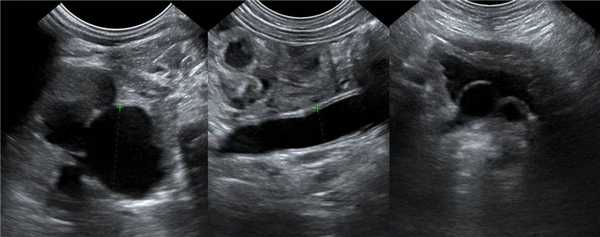

На УЗИ в мочевом пузыре или в уретре определяется анэхогенное образование, округлой формы, с четким и ровным контуром; соответствующий мочеточник обычно заметно расширен; может присутствовать гидронефроз верхней части удвоенной почки. Уретероцеле определяют как внутрипузырные (полностью внутри мочевого пузыря) или внепузырные (некоторая часть постоянно расположена в шейке мочевого пузыря или в уретре).

Рисунок. У новорожденного на УЗИ почек определяется гидронефроз (1) и расширенный мочеточник (2) справа. В мочевом пузыре двустороннее уретероцеле (3). При исследовании левой почки структурных изменений не выявлено.

Рисунок. На УЗИ определяется удвоенная чашечно-лоханочная система, расширена лоханка верхнего сегмента (1) и мочеточник на всем протяжение (2, 3), в мочевом пузыре уретроцеле (4). Полное или неполное удвоение чашечно-лоханочной системы возможно увидеть с помощью КТ-урографии.

Рисунок. Дистальный отдел мочеточника расширен, в мочевом пузыре анэхогенное образование с тонким и ровным контуром — уретероцеле.

Рисунок. Двустороннее уретероцеле на УЗИ: в режиме ЦДК из верхушек уретероцеле определяется выброс мочи.

Рисунок. На УЗИ в уретероцеле определяется гиперэхогенная структура с акустической тенью — камень. Уретероцеле может являться одним из факторов, способствующих камнеообразованию.